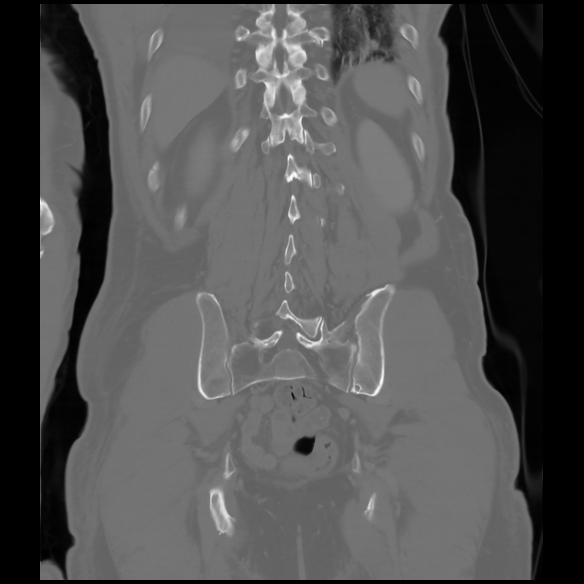

6 CUERPO,CE,Coronal,3.000,CUERPO,Coronal,